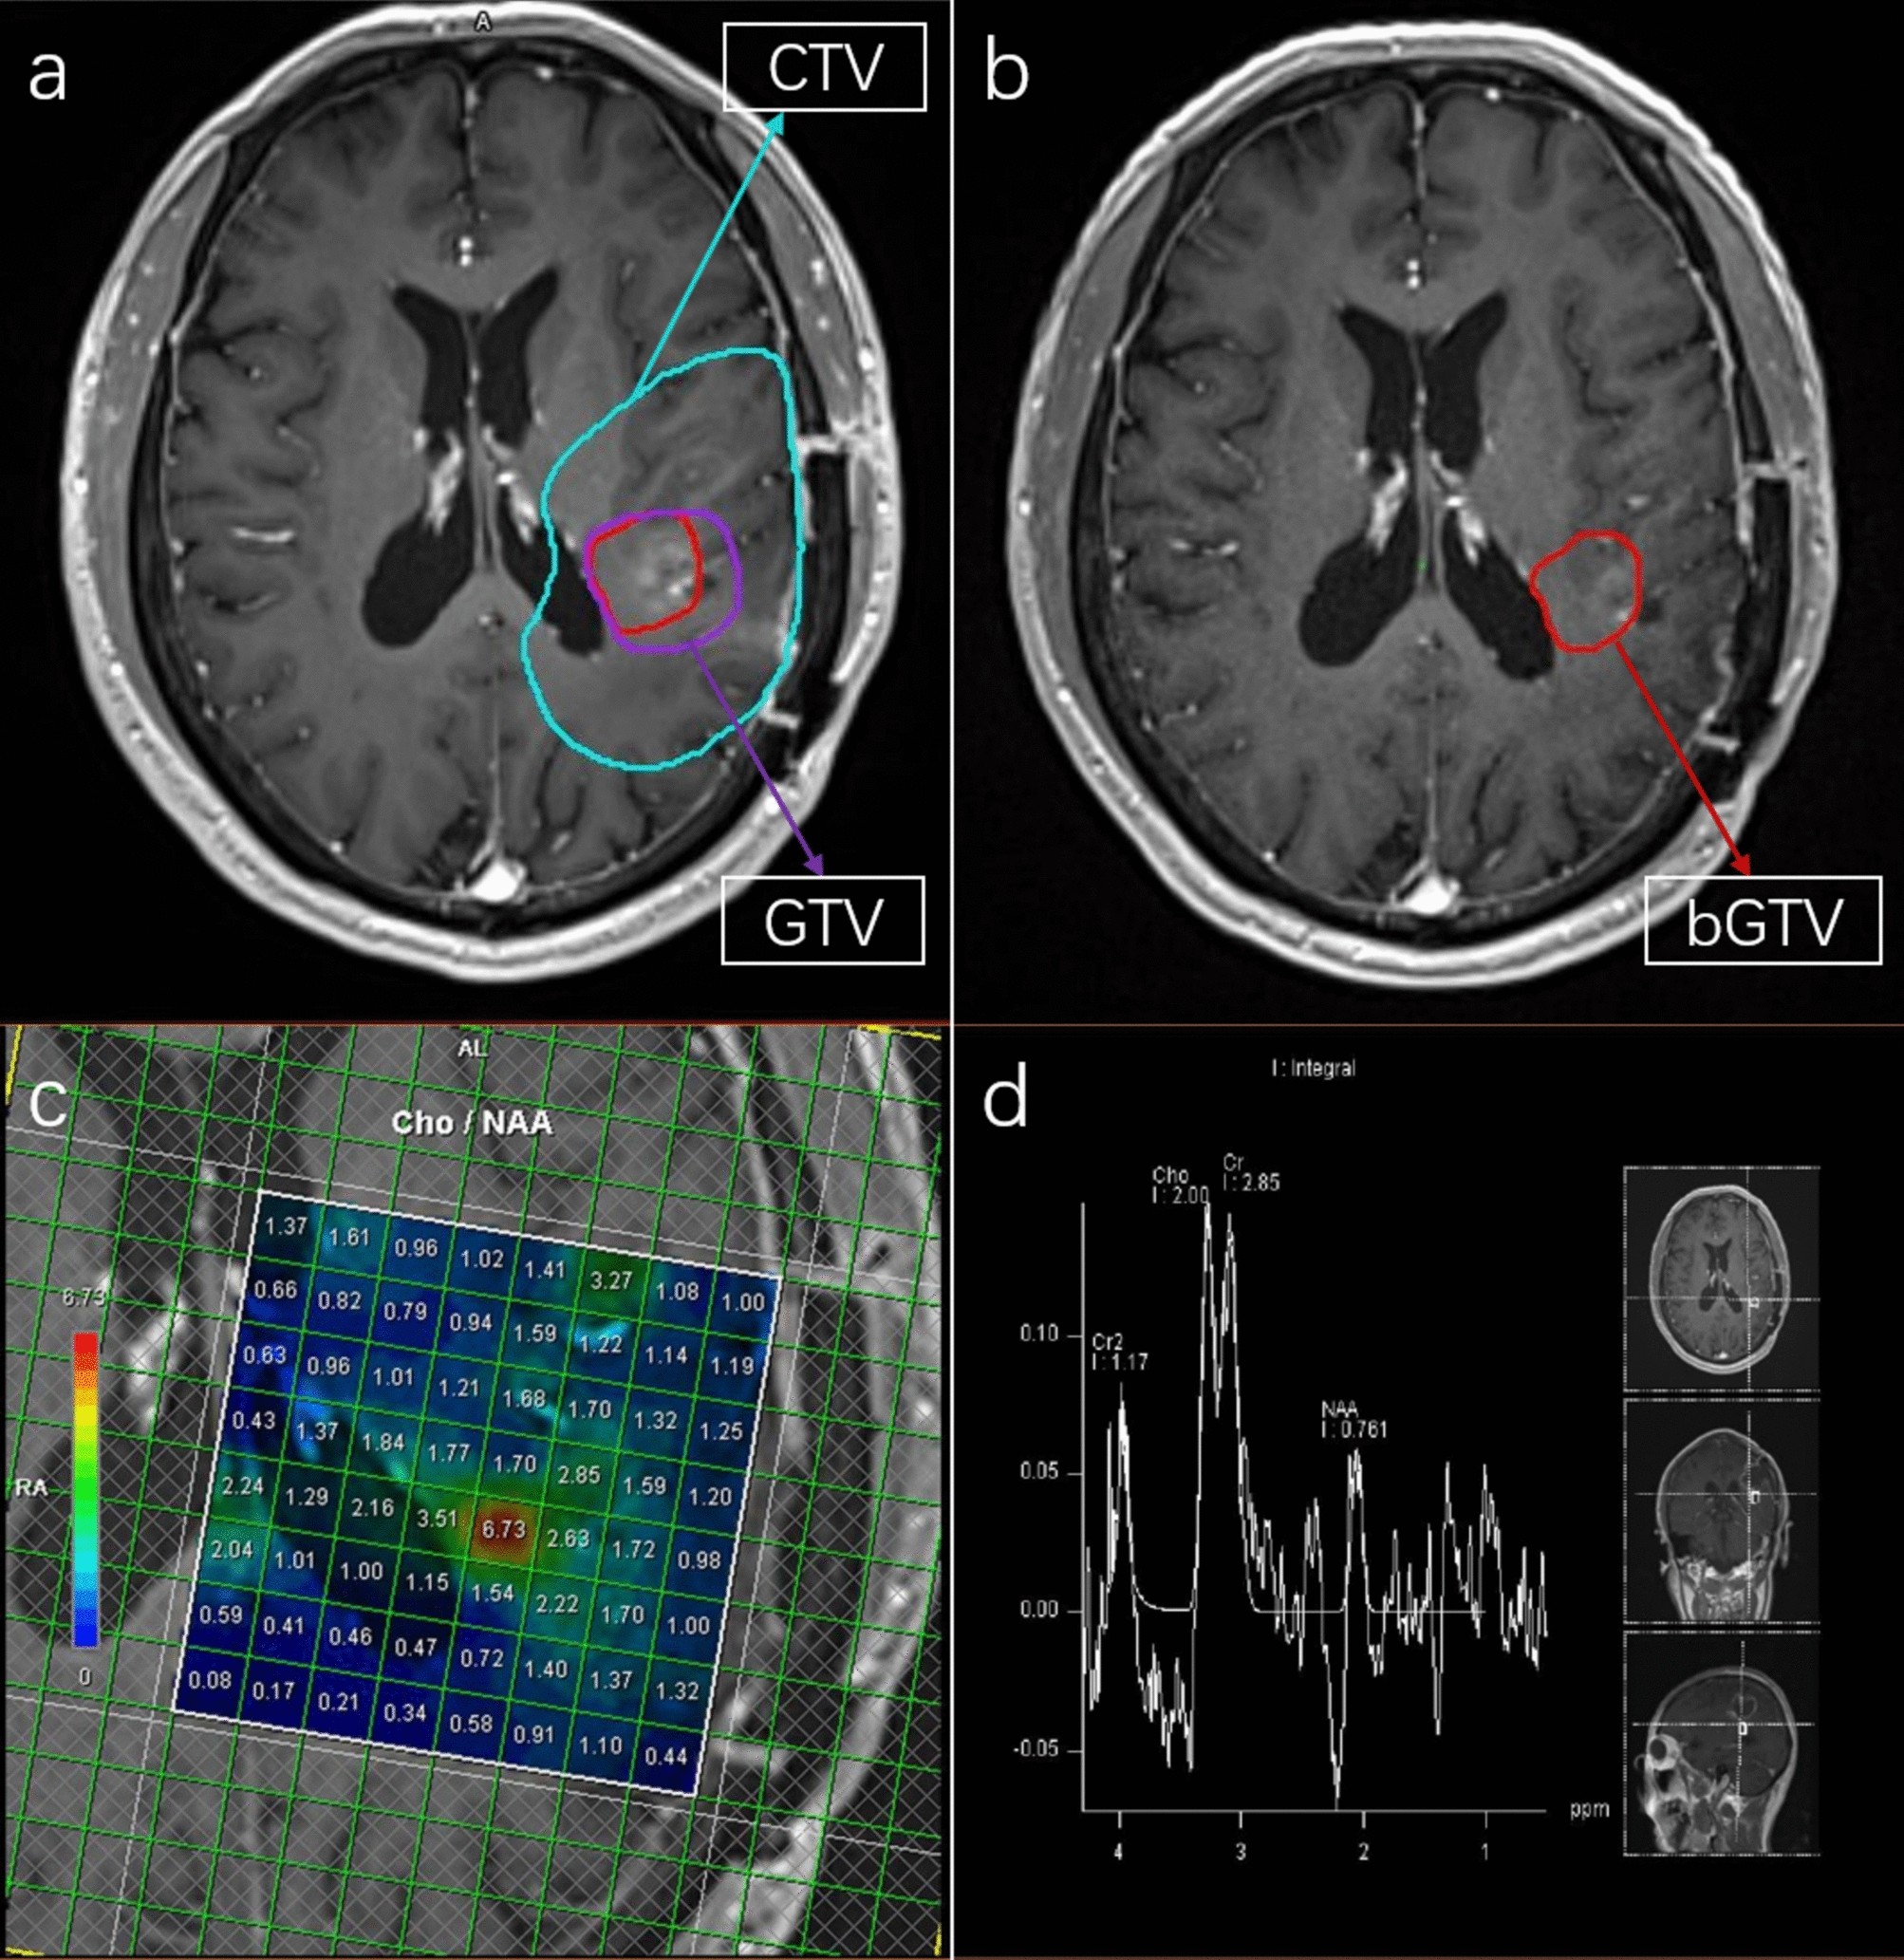

High-risk tumor regions as determined by MRS after standard radiotherapy in patients with GBM: (a) T1-weighted sequence before radiotherapy; (b) bGTV in T1-weighted sequence after a 60 Gy dose; (c, d) regions of interest showing the Cho/NAA ratio.